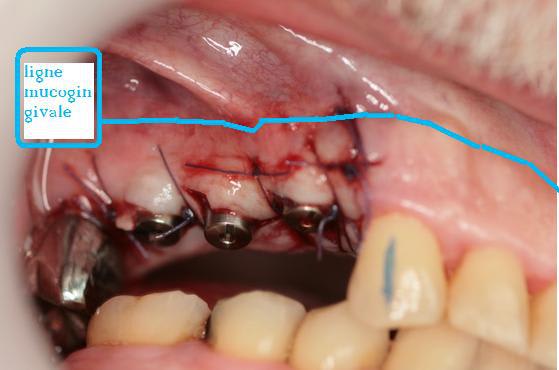

non je ne pense pas car boulevard de GA mais si cela avait été le cas j'aurai planifié un incision en demi épaisseur en palatin puis pleine épaisseur à partir de la crète .

Ligne muccogingivale mw7v2s - Eugenol

J'avais mal vue , tu as raison, c'est bon pour la GA.

bon boulot.